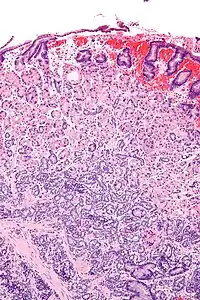

Micrograph of a neuroendocrine tumour of the stomach. H&E stain. | |